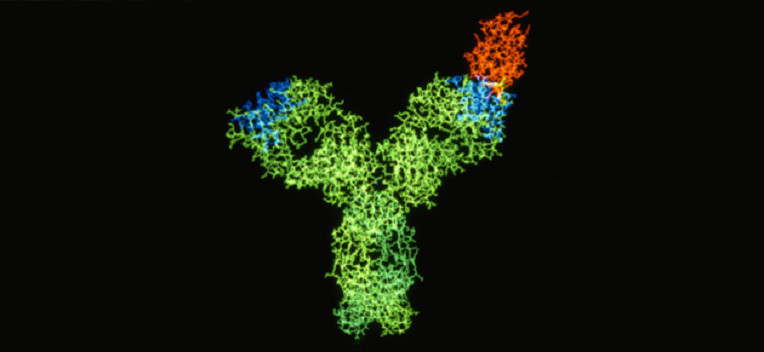

Ganymed develops highly selective antibody against stomach/esophagus cancer in his advanced stages of clinical trials. The majority of 21 patients treated in a phase IIa trial showed a significant slow-down of the cancer, Ganymed has now recruited 210 patients for a phase IIb trial.